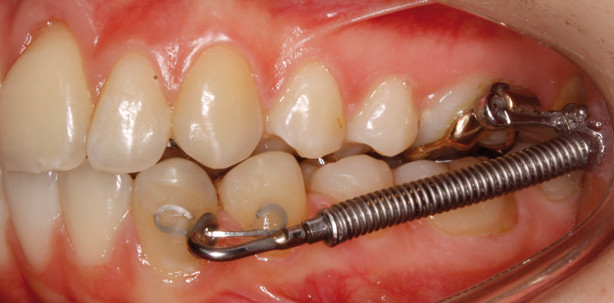

Epidemiologische Untersuchungen zeigen, dass der Distalbiss mit seinen Unterklassifizierungen Angle Klasse II/1 und II/2 die häufigste Bissanomalie in der kaukasischen Bevölkerungsgruppe darstellt.2,4 Für die Behandlung von Klasse II-Malokklusionen finden eine Vielzahl an verschiedenen bi- oder unilateralen festsitzenden Klasse II-Mechaniken Verwendung, wie z. B. die ForsusTM-Apparatur der Firma 3M Unitek (Abb. 1). Hierbei handelt es sich um eine kooperationsunabhängige Distalisierungsapparatur, die als dreiteilige, teleskopierende Federkomponente aus einer Koaxialfeder, einem Druckstab (Pushrod) und einem EZ2-Modul zusammengesetzt ist. Die Koaxialfeder besteht aus einer superelastischen Nickel-Titan-Druckfeder und umhüllt die Außenseite des Federmoduls. Der Druckstab weist an seinem freien Ende eine Schlaufe zur Befestigung am Unterkieferbogen der Multiband-Multibracket-Apparatur auf und ist in sechs verschiedenen Längen (22 mm bis 38 mm) verfügbar.

Das Teleskopelement wird mit dem Druckstab kombiniert, indem dieser in das Federmodul eingeführt wird. Die ForsusTM- Apparatur kann ohne Laborprozess direkt im Mund des Patienten intermaxillär eingesetzt werden, ohne dass hierfür Brackets oder Bögen entfernt werden müssen. Am Oberkiefer wird die ForsusTM-Apparatur mit dem „Click-in- place“-Clip (EZ2-Modul) befestigt, indem dieser in das Molarenröhrchen eingeführt wird und aufgrund seiner Passform und des Anti-Rotationsarms stabil arretiert. Im Unterkiefer wird die Schlaufe des Druckstabes distal des Unterkiefereckzahns von okklusal auf den Bogen gesetzt, bei Vestibulär-Apparaturen am Unterkieferbogen, bei Lingualapparaturen am gesondert geklebten Teilbogen bzw. Eckzahnband (siehe später im Text) und zur Sicherung mithilfe einer Flachzange um den Bogen geschlossen. Die teleskopierende Koaxialfeder erlaubt eine normale Mundöffnung und gestattet durch ihr offenes Federdesign eine erleichterte Mundhygiene. Aufgrund der günstigen physikalischen Eigenschaften der superelastischen NiTi-Feder zeichnet sie sich durch relativ konstante Kräfte aus, die sich bei geschlossenem Mund weitgehend horizontal voll entfalten und über die gesamte Anwendungsdauer nahezu gleichmäßig stark bleibt. Neben einer effektiveren Zahnbewegung hat dies auch eine längere Haltbarkeit der Mechanik aufgrund fehlender Ermüdungsbrüche zur Folge.